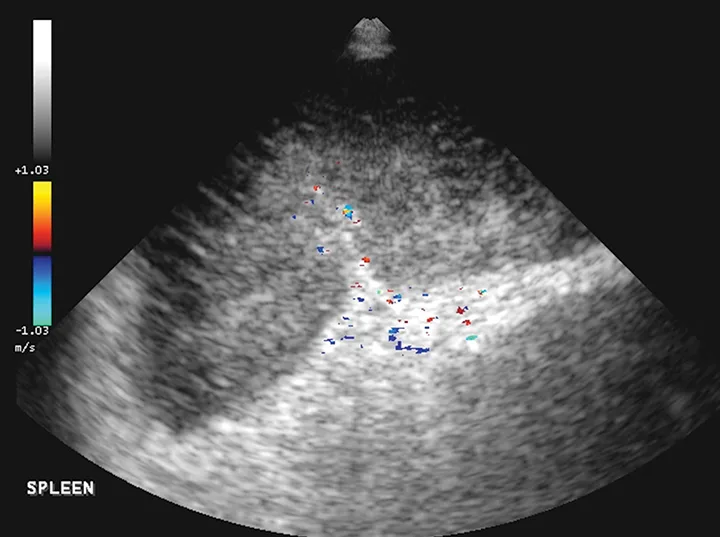

Featured Image

FIGURE 6

The spleen is markedly enlarged, hypoechoic, and lacy, with hyperechoic patches surrounding the hilus. A perivenous hyperechoic triangle at the splenic hilus is continuous with the mesentery, and no flow is present on Doppler. These findings are often associated with splenic torsion.20